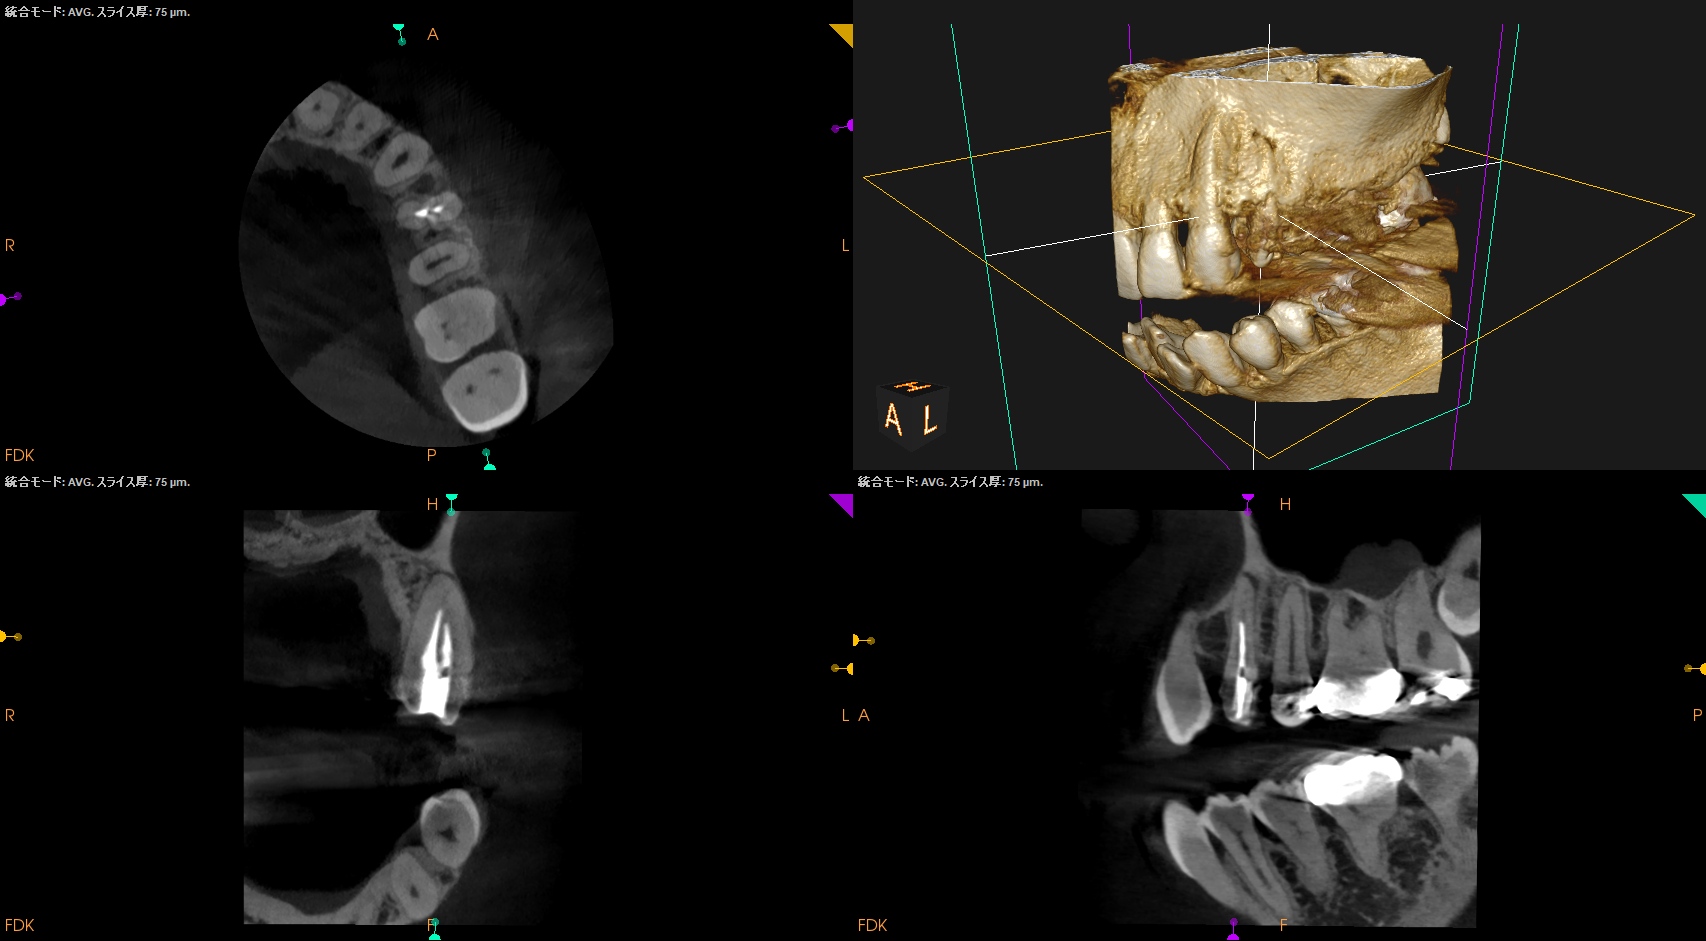

以下のようなケースでも可能なのだろうか?

私(当時Resident)も、

その後の二人のEndodontist(“自称”ではなく、“米国歯内療法学会”が認定する“Endodontist”である)も穿通させられなかったのだ。

何が言いたいか?と言えば、

全ての根管が穿通するとは限らない

ということである。

例えPAやCBCTで根管が見えていても、だ。